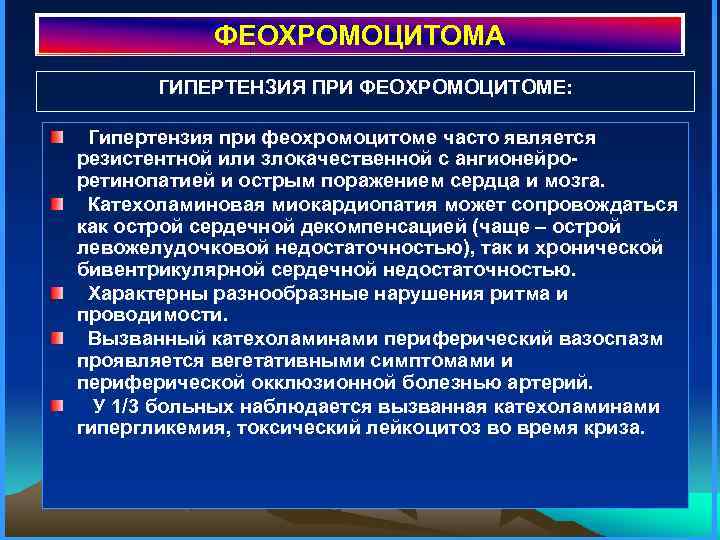

ФЕОХРОМОЦИТОМА ГИПЕРТЕНЗИЯ ПРИ ФЕОХРОМОЦИТОМЕ: Гипертензия при феохромоцитоме часто является резистентной или злокачественной с ангионейроретинопатией и острым поражением сердца и мозга. Катехоламиновая миокардиопатия может сопровождаться как острой сердечной декомпенсацией (чаще – острой левожелудочковой недостаточностью), так и хронической бивентрикулярной сердечной недостаточностью. Характерны разнообразные нарушения ритма и проводимости. Вызванный катехоламинами периферический вазоспазм проявляется вегетативными симптомами и периферической окклюзионной болезнью артерий. У 1/3 больных наблюдается вызванная катехоламинами гипергликемия, токсический лейкоцитоз во время криза.

ФЕОХРОМОЦИТОМА ГИПЕРТЕНЗИЯ ПРИ ФЕОХРОМОЦИТОМЕ: Гипертензия при феохромоцитоме часто является резистентной или злокачественной с ангионейроретинопатией и острым поражением сердца и мозга. Катехоламиновая миокардиопатия может сопровождаться как острой сердечной декомпенсацией (чаще – острой левожелудочковой недостаточностью), так и хронической бивентрикулярной сердечной недостаточностью. Характерны разнообразные нарушения ритма и проводимости. Вызванный катехоламинами периферический вазоспазм проявляется вегетативными симптомами и периферической окклюзионной болезнью артерий. У 1/3 больных наблюдается вызванная катехоламинами гипергликемия, токсический лейкоцитоз во время криза.